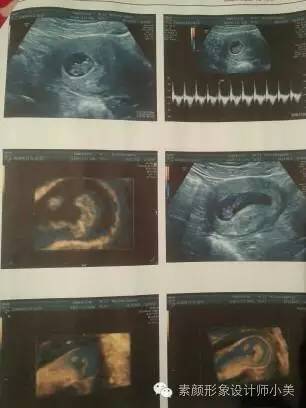

9周胎儿发育

进入第9周,你的胚胎从现在开始能够称为“胎儿”了,也能够称之为“小宝宝”。为了接纳新居民,你的子宫膨胀得非常大,现在胎儿的尺寸大约有25毫米,而且胎儿许多位置都有所改变,如胚胎期的小尾巴不见了等。现在所有的器官、肌肉、神经开始工作。手部从手腕开始变得稍微有些弯曲,双脚开始摆脱蹼状的外表,眼帘开始覆盖住眼睛。